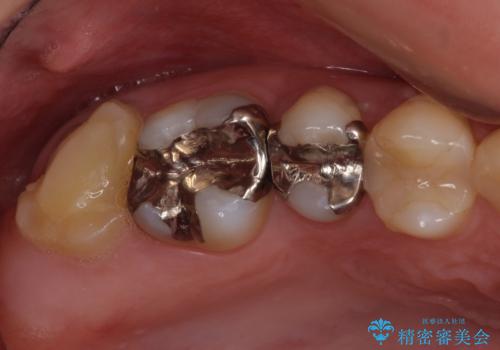

- 右上下の奥歯がむし歯でしみたり痛んだりするとのことで来院された患者様です。

下顎の奥歯は強い痛みを感じており、既に歯髄に不可逆的な炎症が起きていると診断されたため、根管治療の後にセラミッククラウンにて補綴治療を行うこととしました。

上顎の奥歯は最近銀歯による治療を行ったとのことでしたが、適合が不十分であり隙間からしみていたため、適合の良いゴールドインレーにて修復治療を行うこととしました。